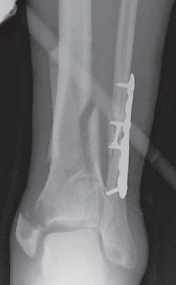

C TECH FIG 1 • A–C. Imaging of 43-C3 plafond injury with anteromedial cortical split allowing best access to injury through anteromedial A B approach.

62.

An anterior plate location is often best for neutralization or buttressing of complex intra-articular fractures. TECH FIG 5 • A,B. Lag screws are used and anterior plating is performed to optimize fixation of the articular segment with a raft of anterior–posterior screws. Autograft from the tubercle of Gerdy was used above the disimpacted articular surface, but allograft or substi- A B tutes may be used.